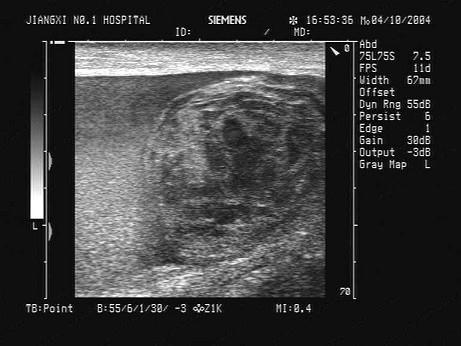

问题 某患者,左阴囊肿大,疼痛,数小时前曾与人殴斗。根据超声声像图,最可能的诊断为?(?)

选项 A.睾丸鞘膜积液 B.阴囊内血肿及血块 C.睾丸破裂 D.睾丸扭转 E.睾丸肿瘤

答案 B